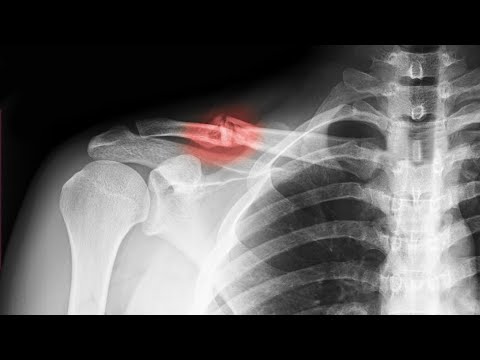

Сегодня расскажу как вообще это произошло, сколько я ходил со сломанной костью не подозревая об этом, случай сказочный, маловероятный, но все таки реальный. Может кому то это будет полезно, и он не повторит моих ошибок. Мой второй канал про который я упоминаю в ролике @TONYSTFU1 Не забудь подписаться и поставить лайк, если понравилась история) А я пойду пока что приводить себя в порядок, и готовить мотоцикл к тренировкам😎 #травма #перелом #мотокросс